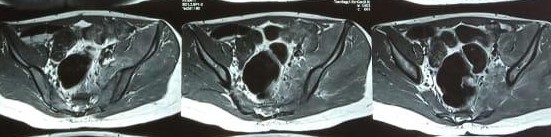

Such kind of unusual presentation involving more than one joint can occur in few conditions like disseminated infection, autoimmune diseases, cancer etc. Looking to the event of Chickenpox, I suspected deep seated infection. I advised MRI scan of right shoulder, spine and left gluteal region. His blood culture, the test to find out the species of invading organism, was ordered. I also sent investigations to rule out autoimmune disease. His MRI of left gluteal region suggested multiple collections of fluid within and surrounding muscles of hip joint. MRI of spine suggested swelling in lower vertebras and swelling of a joint in the pelvic bone (Secro-Iliac joint). His MRI of right shoulder also suggested similar collections and severe damage to one of the muscles of his shoulder joint. The fluid within the pockets was aspirated and sent for evaluation of the organisms involved but did not revealed any organism. His blood culture report sent two days before became available now. It suggested a very dangerous organism MRSA (methicillin Resistant Staphylococcus Aureus). This is a notorious organism that invades in to the blood through a breach in the skin. This boy had chickenpox. The blisters of the chickenpox eroded the skin and paved way for the organisms to enter his blood stream. In the blood the organisms escaped his immune system and multiplied, travelled and settled at regions of spine, left hip and right shoulder and created multiple abscesses. If effective treatment not initiated soon, his joints may get permanently damaged.

He responded well to the appropriate antibiotic treatment. Fever subsided after three days and pain in right shoulder disappeared completely. After a week of treatment was able to walk without pain. His appetite improved. Now he was able to perform his daily activities without support. He was discharged before two weeks with further instructions. He did well at home. He came for the follow up after two weeks. Repeat MRI showed significant improvement compared to previous scan.